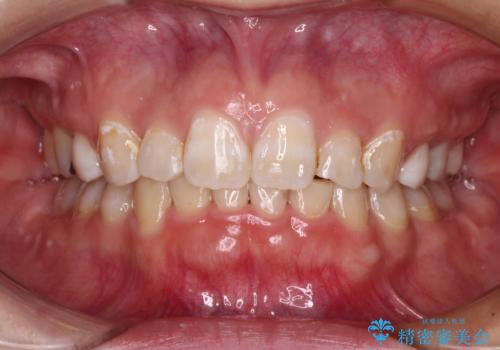

著しい過蓋咬合の改善が必要であった割には、治療期間は2年強と標準的でした。

八重歯は3,4か月で速やかに改善されました。